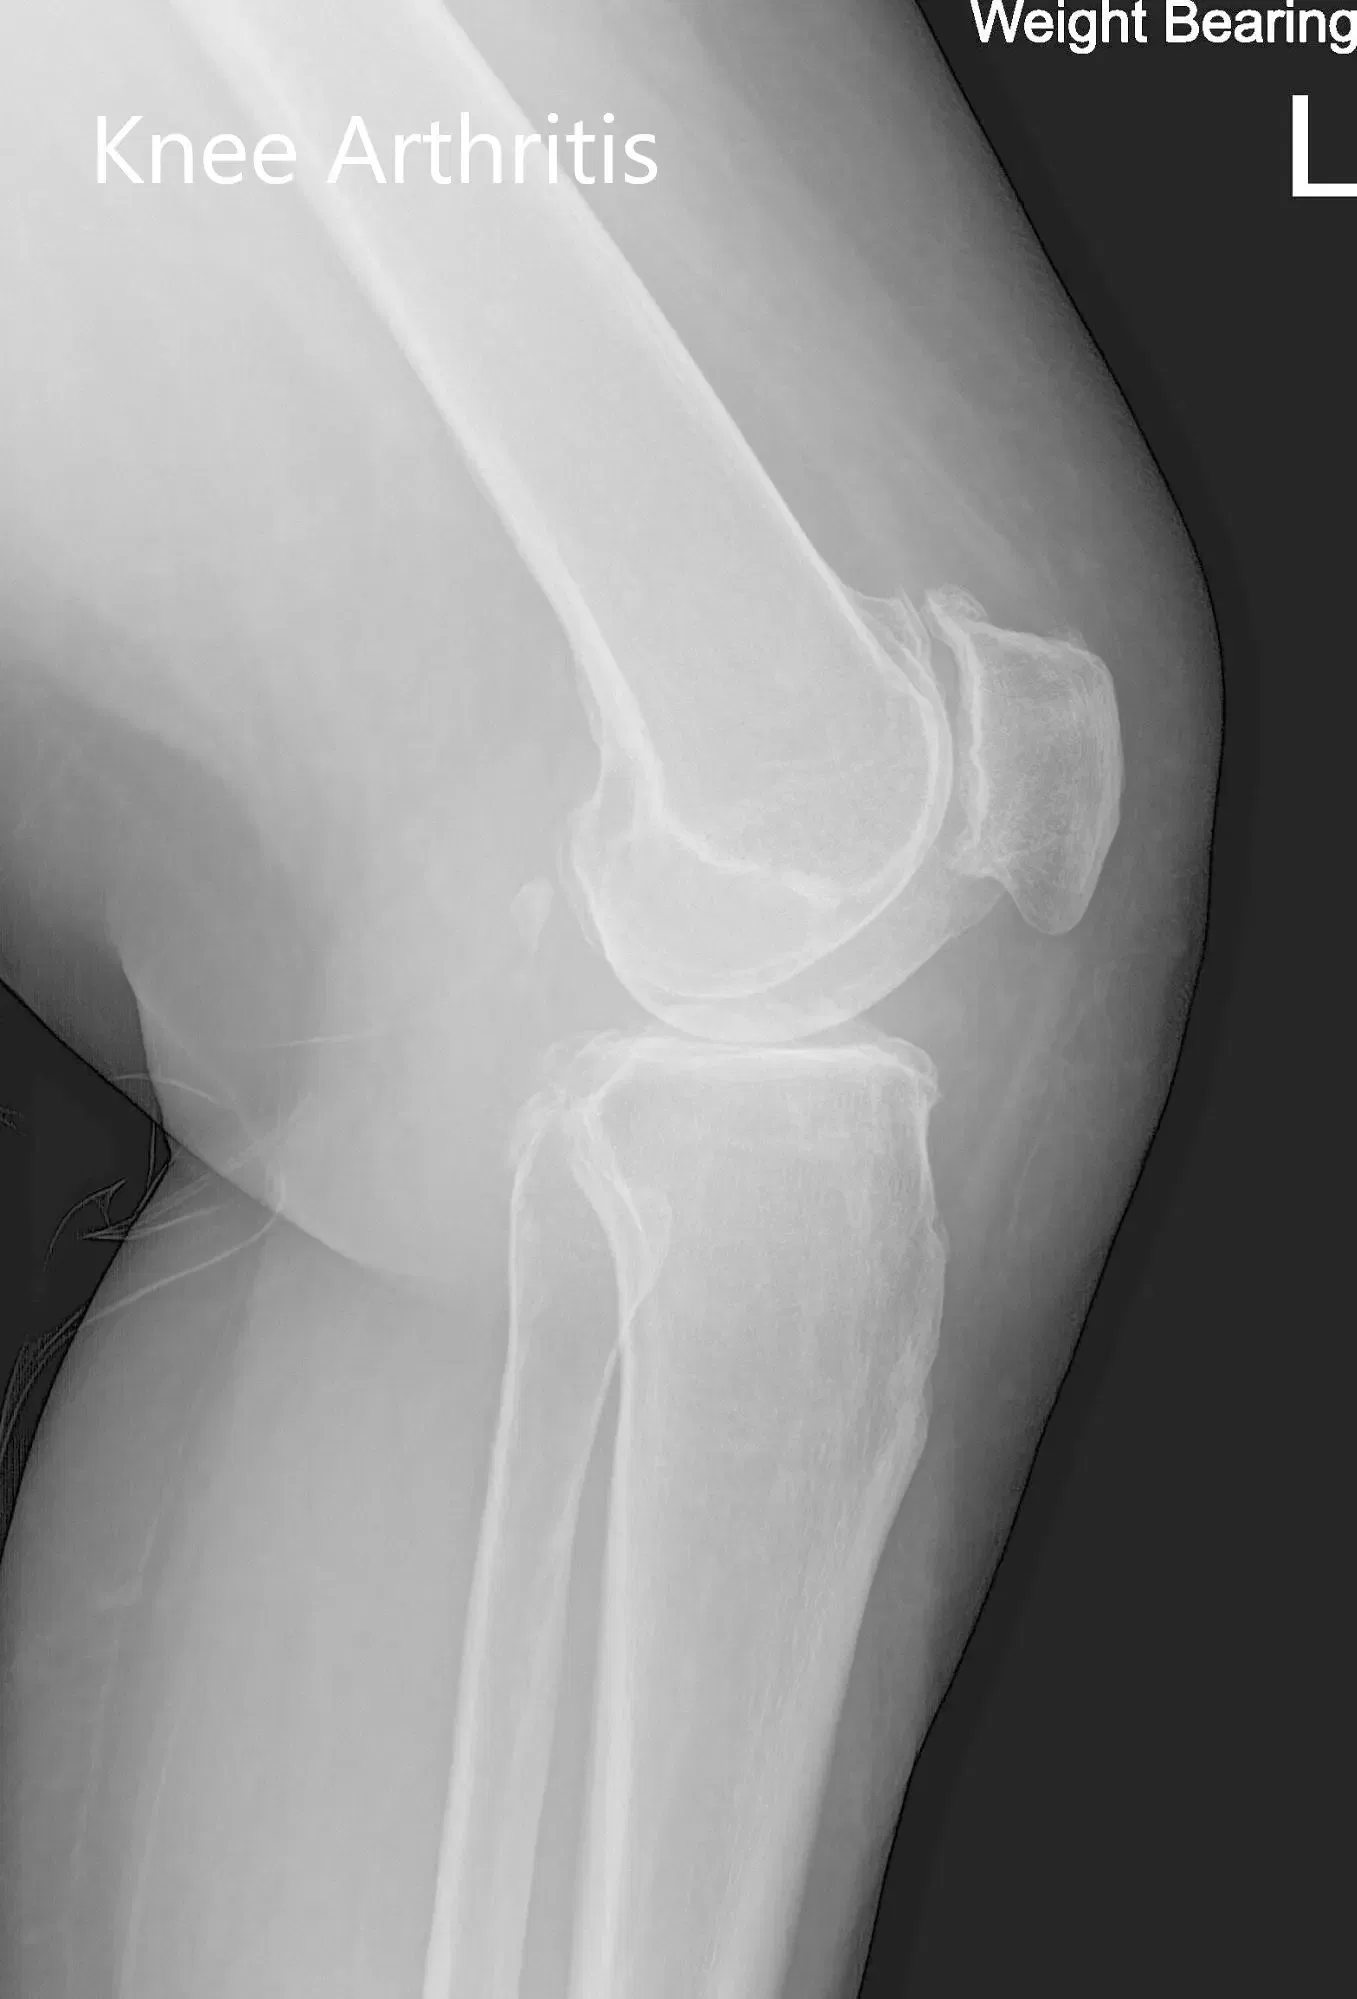

Sus estudios de imagen revelaron cambios osteoartríticos en la rodilla izquierda. Tras considerar cuidadosamente el dolor de rodilla que limitaba el estilo de vida y su condición médica, se le recomendó un reemplazo total personalizado de la rodilla izquierda. Se discutieron extensamente con él riesgos, beneficios y alternativas. Estaba motivado para volver a su rutina diaria sin dolor de rodilla.

Radiografía preoperatoria de la rodilla izquierda que mostró vistas AP y laterales